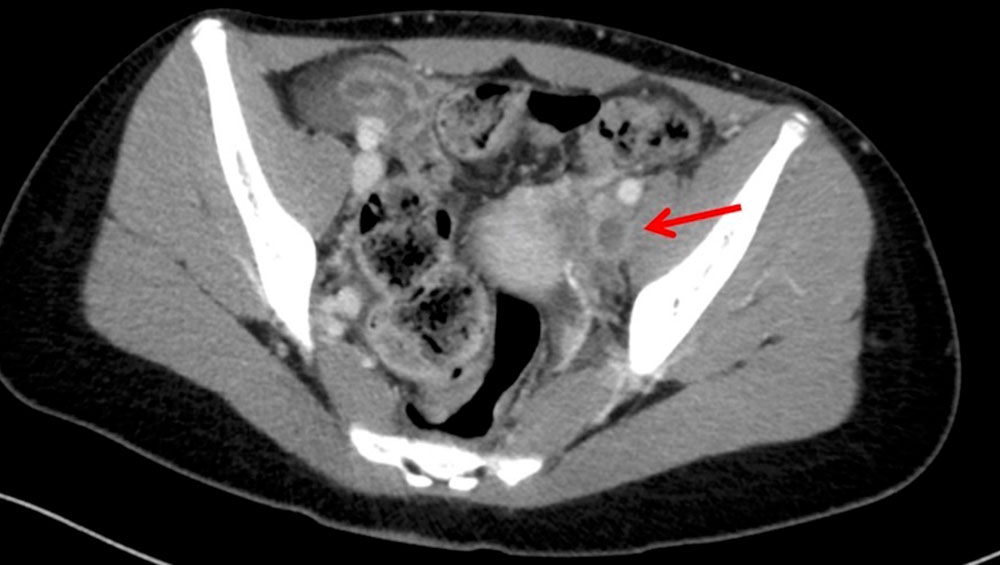

In the case of thrombosis of the central iliac veins, it may be difficult to detect thrombosis by transabdominal sonography because of overlaying structures such as bowel. Phlebography may also produce a false negative in this case. Cross-sectional computed tomography or magnetic resonance imaging may be helpful in such cases if a therapeutic consequence can be derived from it. A good alternative, especially in the area of the proximal common iliac veins, e.g., in May-Thurner syndrome, is intravascular ultrasound, which involves inserting a catheter with an integrated ultrasound probe directly into the vein.